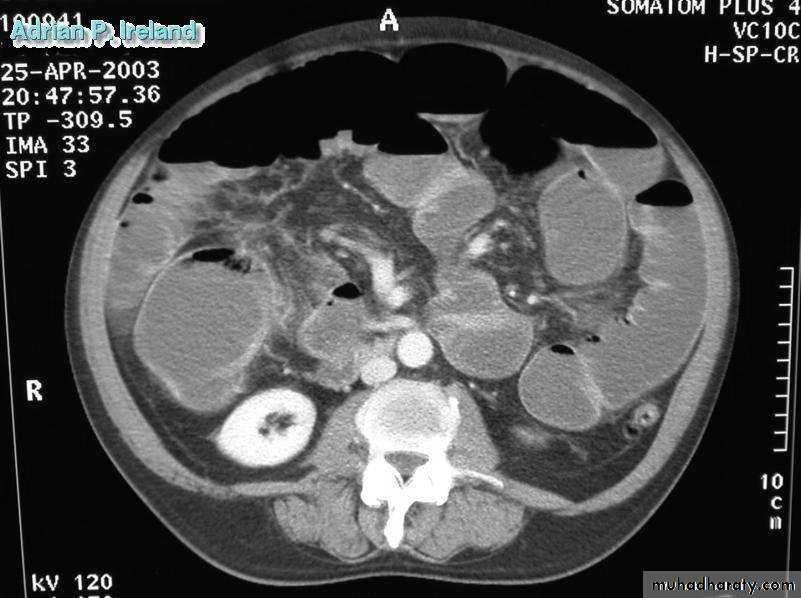

• Radiology; CT, Large bowel obstruction